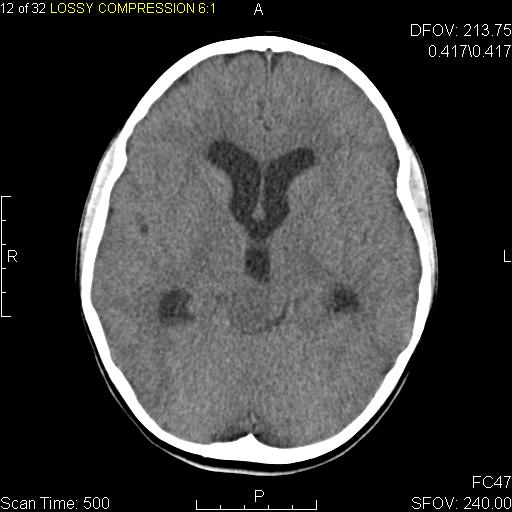

Metastatic tumors to the central nervous system (CNS) typically appear at the gray-white matter junction as a number of distinct lesions.

Radiology of oligodendrogliomas typically show a calcified tumor involving the central nervous system (CNS).

Radiology of craniopharyngiomas typically shows calcifications.